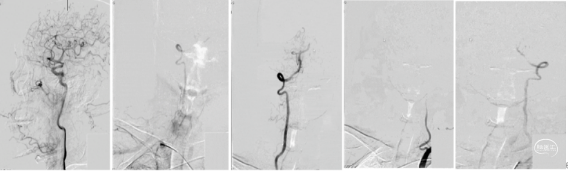

手术过程:右侧股动脉置入8F 股动脉鞘,主动脉弓及超选造影提示右侧颈内动脉闭塞-栓塞性病变(大负荷量栓塞)。

泥鳅导丝携带125cm多功能导管导引088抽吸导管8F 115cm置于颈总动脉,在泥鳅导丝导引下可单独上至海绵窦段。下图1、2

远端通路导管6F 130cm导引心玮吞川抽吸导管到达血栓近端进行第一次抽吸后海绵窦后膝显影,远端仍闭塞,血管迂曲严重。下图3

微导丝、微导管导引6F 130cm远端通路导管越过海绵窦后膝,并导引心玮吞川抽吸导管深入残余血栓进行第二次抽吸,眼动脉显影,眼段以远仍闭塞。

远端通路导管6F 130cm在微导丝及微导管导引下越过虹吸弯,并导引088抽吸导管到达血栓近端,应用其大口径及强负压对血栓进行第三次抽吸,直接原位抽出血栓,血管完全再通,无血栓逃逸及残留。